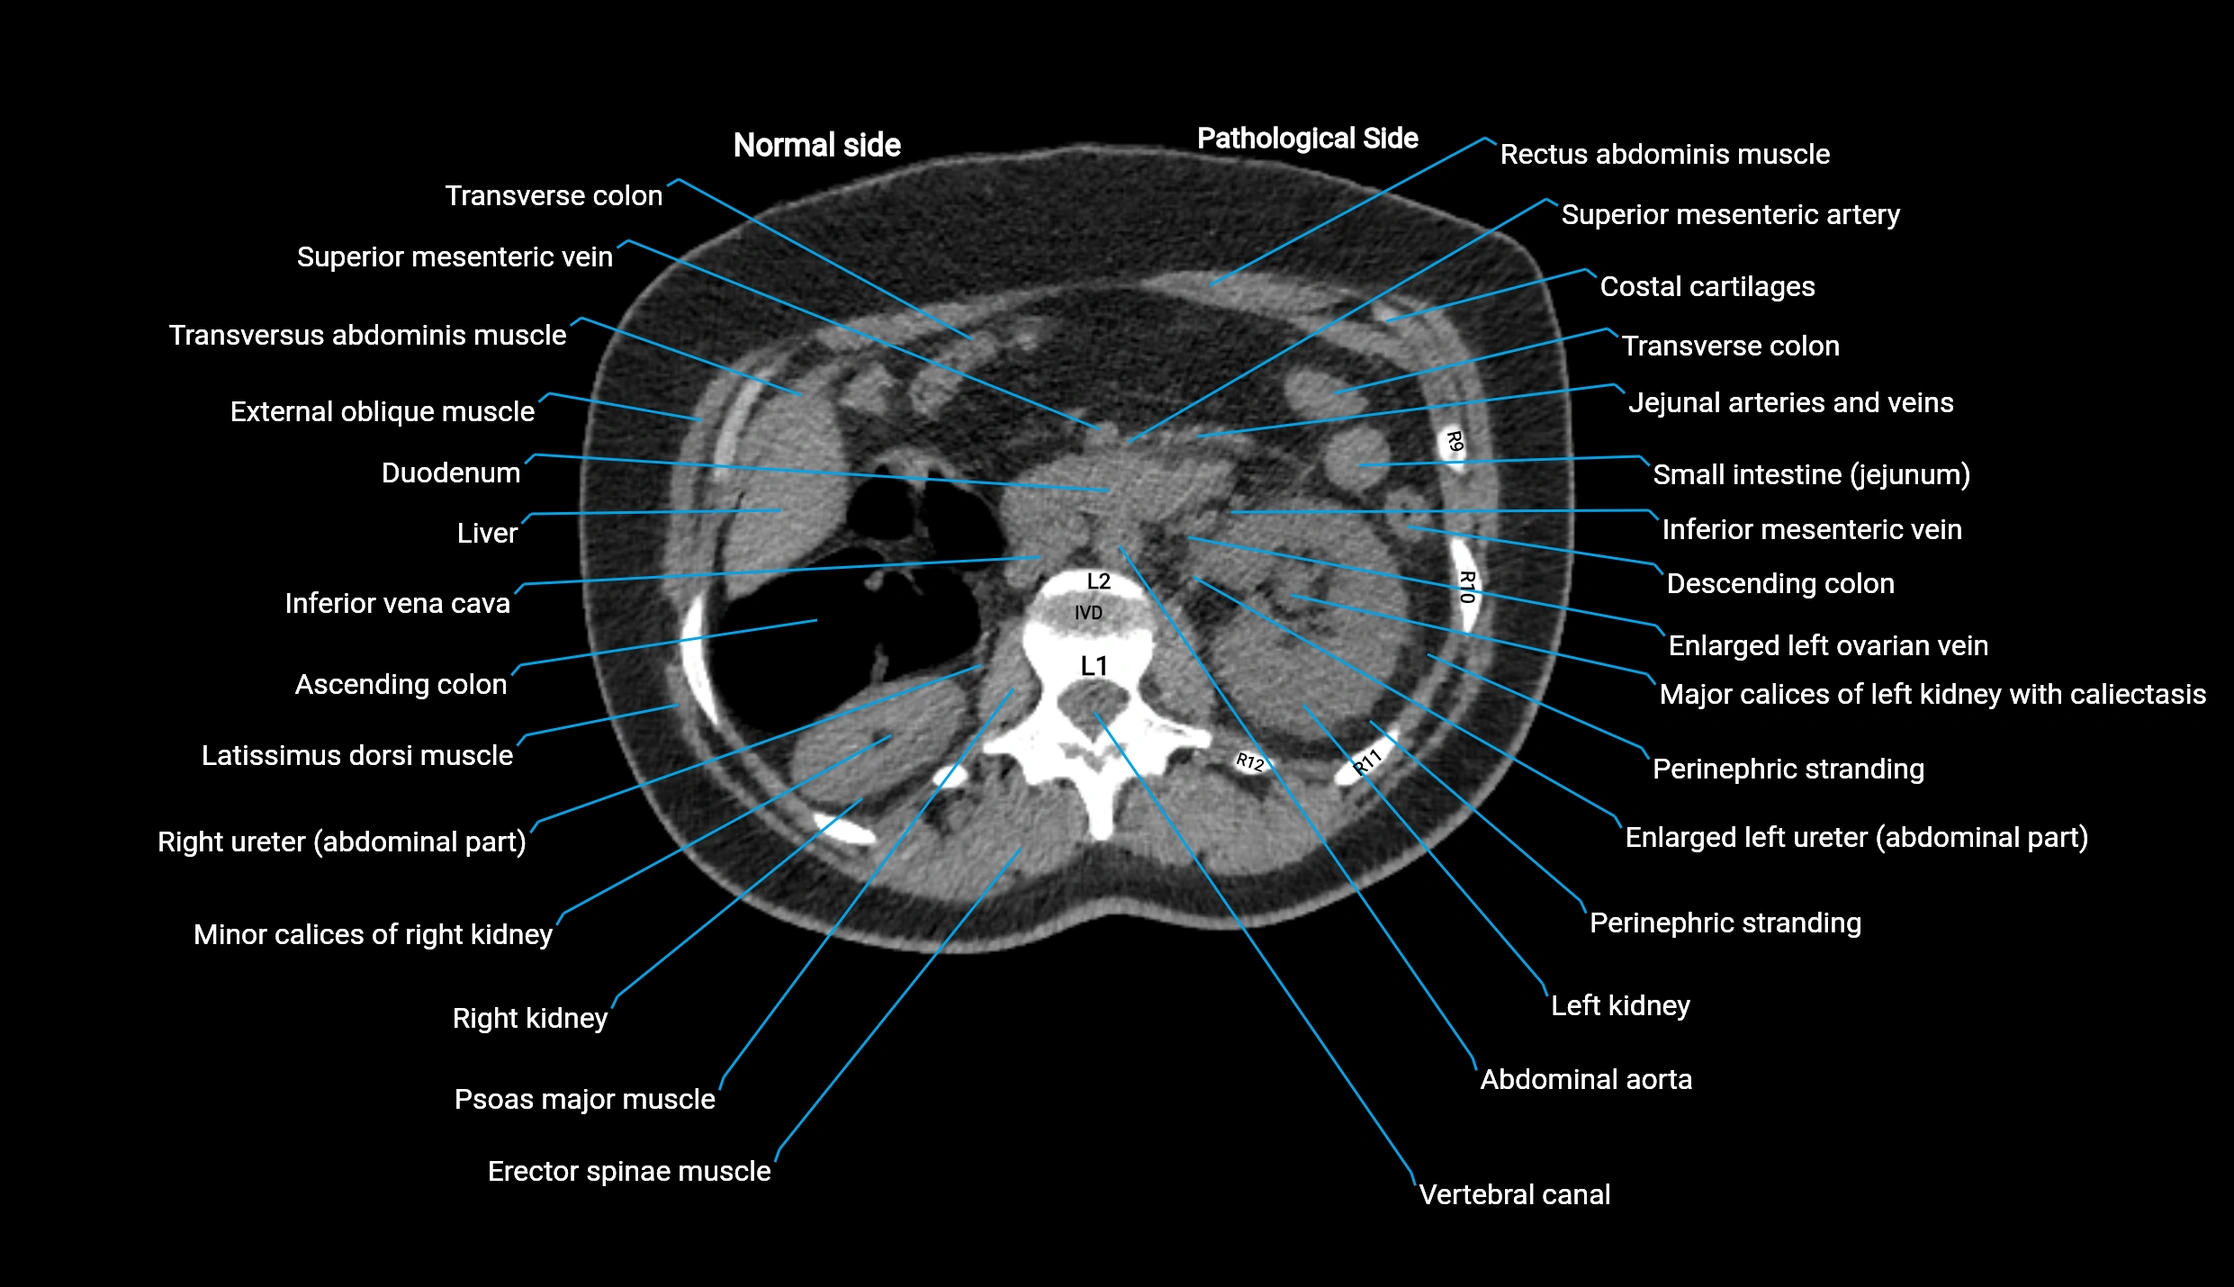

CT image

image